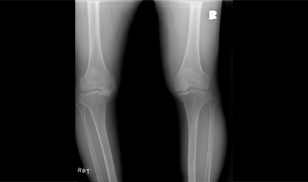

퇴행성 관절염의 진단에서 중요한 것은 증세와 방사선 소견입니다.

보통X-레이를 찍게 되는데, 질병 초기에는 정상이나 점차 진행되면서 X-레이상 관절 간격이

좁아지는대, 특히 체중이 실리는 부위가 비대칭적으로 좁아지게 됩니다 그 외에 연골 아래 부위가

경화되어 하얗게 보이고, 관절면 주위로 뾰족하게 튀어나오는 골극이 형성되기도 합니다.

하지만 X-레이 상에서는 55세 이상의 80% 75세 이상에서는 거의 전 인구가 퇴행성 관절염 소견을

관찰할 수 있으므로, 방사선 소견과 더불어 그에 일치하는 임상 증상이 있어야 퇴행성 관절염이라

진단합니다.